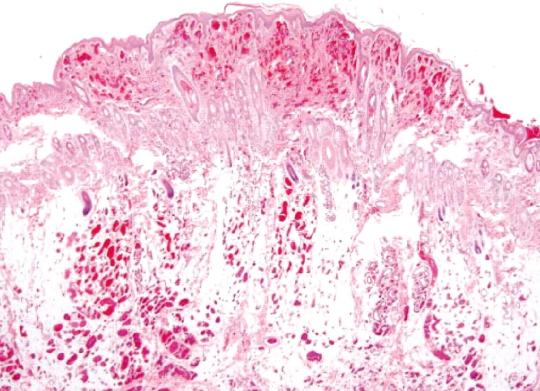

Lilly kommt aus einer deutschen Zucht zur neuen Besitzerin. Von Anfang an wird darauf hingewiesen, dass das Tier eine Geburtsgebrechen habe, welches schon abgeklärt worden sei: Eine Angiomatose am linken Vorderbein. Die neue Besitzerin legt uns den Befund einer Gewebeuntersuchung vor, welcher damals beim Welpen gemacht worden war - aufgrund dieser Hautbiopsie wurde die Diagnose der Gefässveränderung gestellt. Anlässlich der Kastration sehen wir die Hündin das erste Mal.

Nach 10 Tagen werden die Fäden gezogen und die Untersuche besprochen: Das Labor bestätigt den Befund einer Angiomatose; es werden keine Bakterien aufgefunden. Da die Veränderungen gegenwärtig nicht zuzunehmen scheinen und der Hund symptomfrei ist, wird vorderhand abgewartet und keine Therapie eingeleitet.

Angiomatose ist ein Sammelbegriff für verschiedene, auf einer Vermehrung von Blutgefässgewebe basierenden Hautveränderungen. Die bei Hund und Katzen sehr selten auftretenden Veränderungen sind am häufigsten an den Beinen von jungen Tieren anzutreffen und können sich lokal infiltrativ ("einwachsend") verhalten und auch den unterliegenden Knochen schädigen. Es wird angenommen, dass es sich hierbei um eine Missbildung von Hautgefässen handelt, welche möglicherweise einen genetischen Hintergrund hat. Häufig breiten sich die Veränderungen mit der Zeit aus; die Therapie ist (falls möglich) eine chirurgische Entfernung. Es sind Fälle beschrieben, bei welchen im veränderten Gewebe spezielle Bakterien (Bartonella) gefunden wurden, welche möglicherweise die Ursache des Problem darstellen. Eine Spezialfärbung der Gewebeproben von Lilly zeigte allerdings keine Bartonellen.